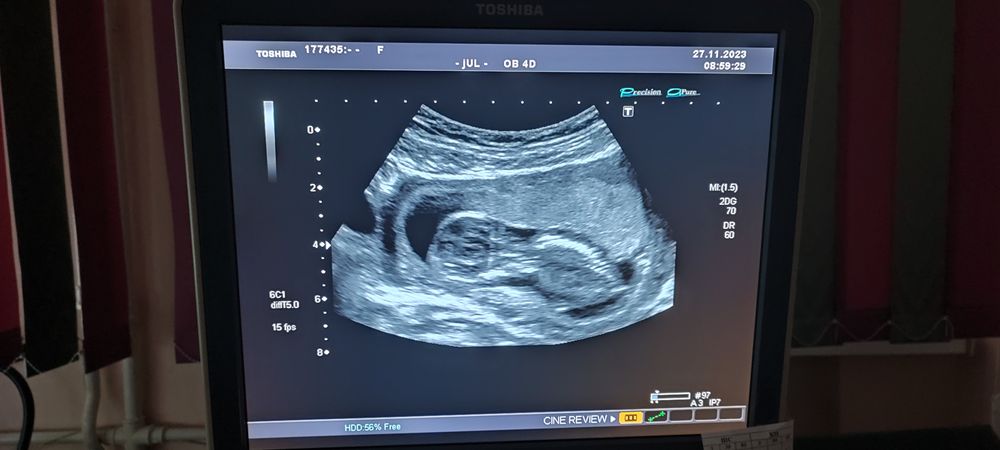

12н6д: первый скрининг💙❤🥰🙏🤗

27.11.2023

Зашла посмотреть, есть ли от вас новости, а тут всё так хорошо 😍❤️ Поздравляю! Забавно, что и этот малыш всех игнорирует и лежит к вам спинкой 😂 Наверное, ему так виднее и удобнее. Пусть всё с крошечкой будет хорошо 🥰 А мой скрининг ровно через неделю. Ждём и пытаемся не паниковать 😂

Ну слава богу, что все хорошо. А вот я поспорю, у малыша голова более угловатая, нежели у Аурики. У мальчиков реально череп более угловатый. Я своих сравнивала и видно даже в 10 недель было. Так, что ждем анализ😉

Катюнечка Солнышко, я же говорю череп пацанячий прям Изображение